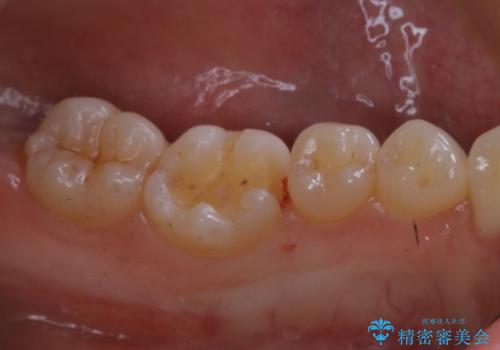

適合のよいセラミックで自分の歯となじむ自然な仕上がりに

- 大きく口を開けると目立つ銀歯のやり替えをご希望された患者様です。適合のよいセラミックインレーで補綴することで、将来的な虫歯発生のリスクを最小限に抑え、機能面でも安心して使っていただけるようにしました

自費診療で用いられる材料は保険適応の材料に比べて、より精密で適合の良い被せ物作ることができるため、長期的な虫歯のリスクを大幅に減らすことが可能です。